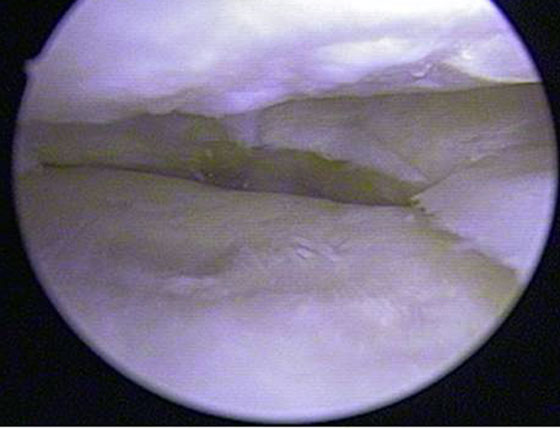

Como primer paso se realiza una Artroscopía. Esta nos permite realizan un diagnóstico de certeza de la lesión, como así también tratar la patología asociada intraarticular (Fig. 1).

Figura 1: Visión artroscópica del compartimiento interno. Lesion Condral avanzada del condilo femoral y platillo interno.